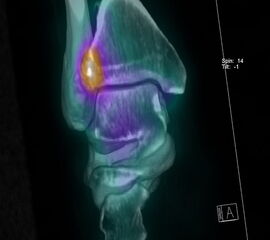

Eine weiteres, relativ neues Verfahren ist die Kombination einer 3-dimensionalen Knochen-Szintigraphie, der sogenannten SPECT (Single-Photon-Emissions-Computertomographie) mit einem CT-Scan, was neue Möglichkeiten in der orthopädischen Diagnostik verschiedener Erkrankungen bietet (Wuest 2007). Die SPECT-CT ermöglicht die szintigraphische Lokalisierung der Osteoblastenaktivität im interessierenden Bereich, in Kombination mit der anatomischen Auflösung eines CT-Scan. So erhält der Chirurg nicht nur morphologische, sondern auch biologische Informationen über OCL 16 oder Impingementkonstellationen 17. Die SPECT-CT zeigt zudem eine hervorragende interobserver und intraobserver Reliabilität 18.

Vergleichsstudien von SPECT-CT zur MRT hinsichtlich Bildinterpretation und Entscheidungsfindung zeigte, dass im Vergleich mit der MRT das SPECT-CT zusätzliche Informationen liefert und somit auch die Therapieentscheidung beeinflusst 1920.

Zur Vollansicht und zum Lesen der Bildbeschreibung bitte das Bild anklicken.